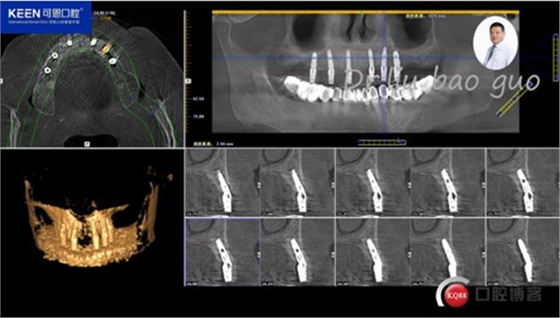

手術(shù)前種植軟件設(shè)計(jì)方案

檢 查:顏面對(duì)稱(chēng),無(wú)腫脹、畸形、腫物及竇道;顳下頜關(guān)節(jié)左右對(duì)稱(chēng),頦點(diǎn)居中,面下1/3協(xié)調(diào)。開(kāi)口度正常無(wú)偏斜,雙側(cè)關(guān)節(jié)動(dòng)度一致,關(guān)節(jié)無(wú)彈響無(wú)雜音;咀嚼肌無(wú)壓痛;17-27缺失,牙齦無(wú)明顯異常,CT示:牙槽骨寬度,高度尚可。